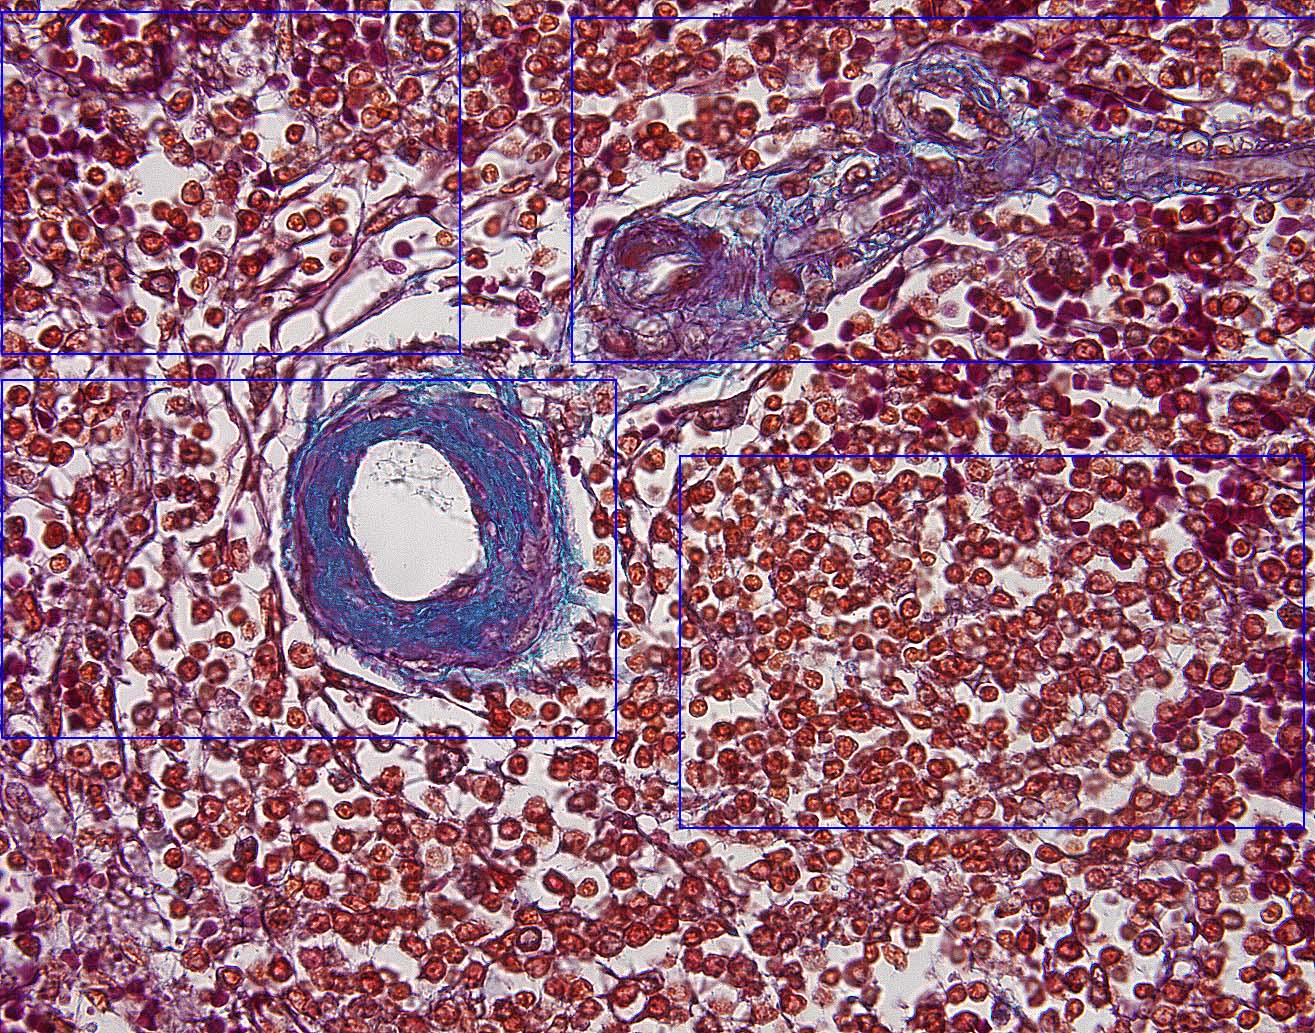

Return To Cartoon of Spleen